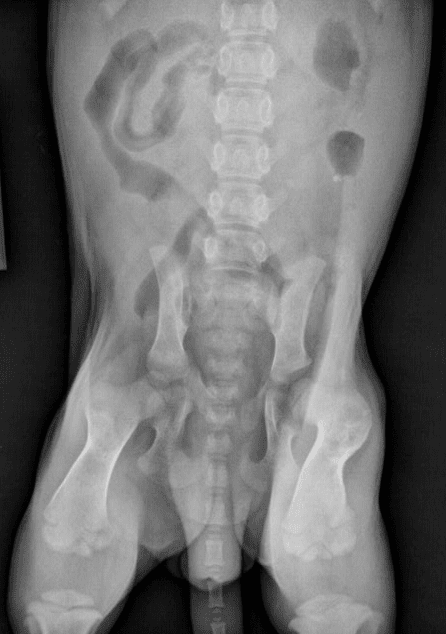

- La radio des hanches n’est pas non plus exempt d’erreurs…

- Mauvaise position du chien à la radiographie

- Mauvaise interprétation à la lecture de la radio des hanches

- La dysplasie des hanches évoluant avec le temps, il est totalement inefficace de radiographier les hanches d’un chien trop jeune… Idéalement, les radios des hanches ne devraient pas être envisagées avant l’âge de trois ans.